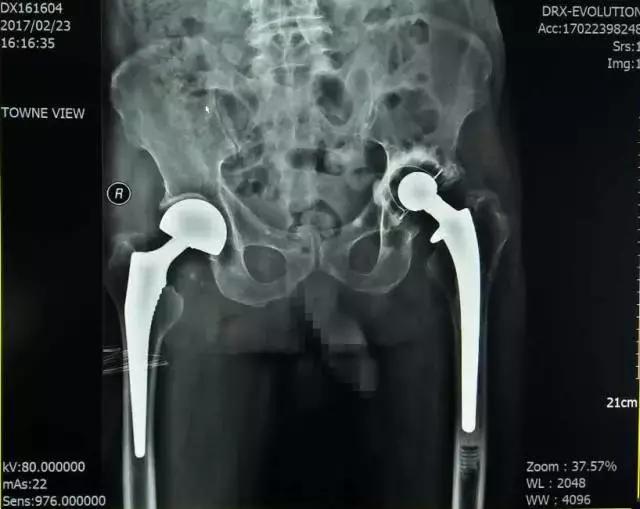

陶XX术后X线

患者陶XX,男,91岁,患者因跌倒致右髋部疼痛、功能障碍3小时就诊。

入院诊断:1.右股骨颈骨折(头下型); 2.骨质疏松症(重度);3.左侧人工全髋关节置换术后。

诊疗措施:患者因右侧股骨颈骨折行右侧人工股骨头置换术。科室专家根据患者情况,以右大粗隆顶点为中点,取右髋后外侧入路,放置合适人工股骨头复位,关节活动度及稳定性合适,术中无副损伤,术后右髋部疼痛明显减轻。

1个月后随访,患者功能改善,生活质量良好。